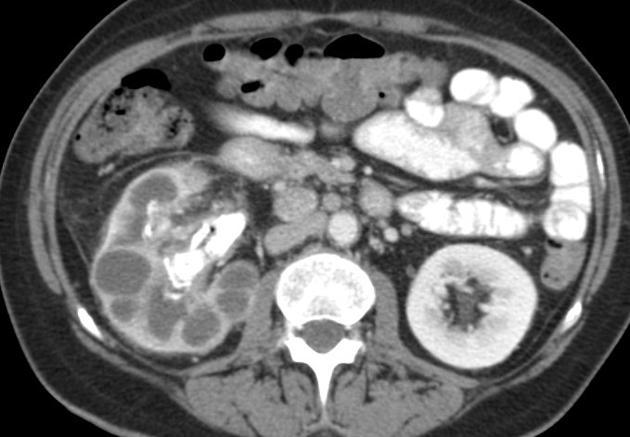

Diagnosis?

Medullary nephrocalcinosis.

95% of cases are due to primary hyperparathyroidism, distal renal tubular acidosis (type 1), or medullary sponge kidneys.

But it can be caused by anything that causes hypercalcemia, hypercalciuria, or hyperoxaluria (others include milk alkalai syndrome, multiple myeloma, hypervitaminosis D, Cushing syndrome).